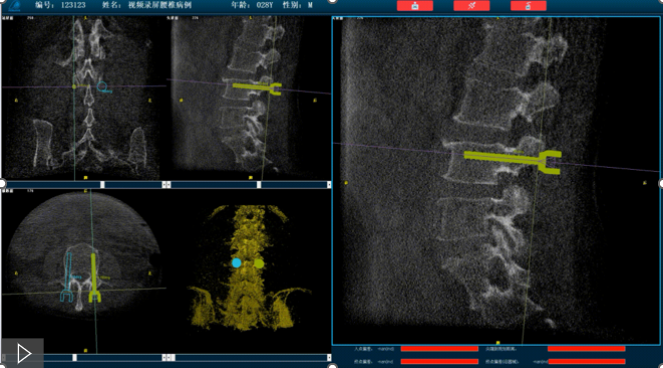

首先,需要明確的是機(jī)器人手術(shù),機(jī)器人在術(shù)中還是做輔助性操作,術(shù)前基于三維C形臂等影像掃描得到骨骼結(jié)構(gòu)的三維數(shù)據(jù),機(jī)器人系統(tǒng)利用手術(shù)規(guī)劃軟件,引導(dǎo)醫(yī)生進(jìn)行可視化預(yù)手術(shù)規(guī)劃(釘?shù)酪?guī)劃、入釘角度),選擇合適的螺釘規(guī)格、尺寸,輔助評(píng)估和及時(shí)調(diào)整手術(shù)路徑規(guī)劃設(shè)計(jì),整臺(tái)手術(shù)都是在主刀醫(yī)生的把控下進(jìn)行操作的。機(jī)器人系統(tǒng)不僅靠譜,而且還提升了手術(shù)的安全性、機(jī)械臂的精準(zhǔn)以及力傳感識(shí)別、實(shí)時(shí)動(dòng)態(tài)追蹤等保護(hù)技術(shù),增加了手術(shù)的準(zhǔn)確性和安全性。

就以普愛(ài)醫(yī)療骨科機(jī)器人PL300B為例,骨科機(jī)器人可以保證亞毫米級(jí)精準(zhǔn)度,例如在脊柱上植入椎弓根螺釘,傳統(tǒng)手術(shù)需要暴露骨組織解剖結(jié)構(gòu),往往會(huì)有10-20cm的開(kāi)口,而使用了手術(shù)機(jī)器人可以將開(kāi)口轉(zhuǎn)變?yōu)閿?shù)個(gè)1-2cm的開(kāi)口,出血量降低至95%以上,大大降低并發(fā)癥的發(fā)生率,同時(shí)有益于病患的更快的術(shù)后恢復(fù)。